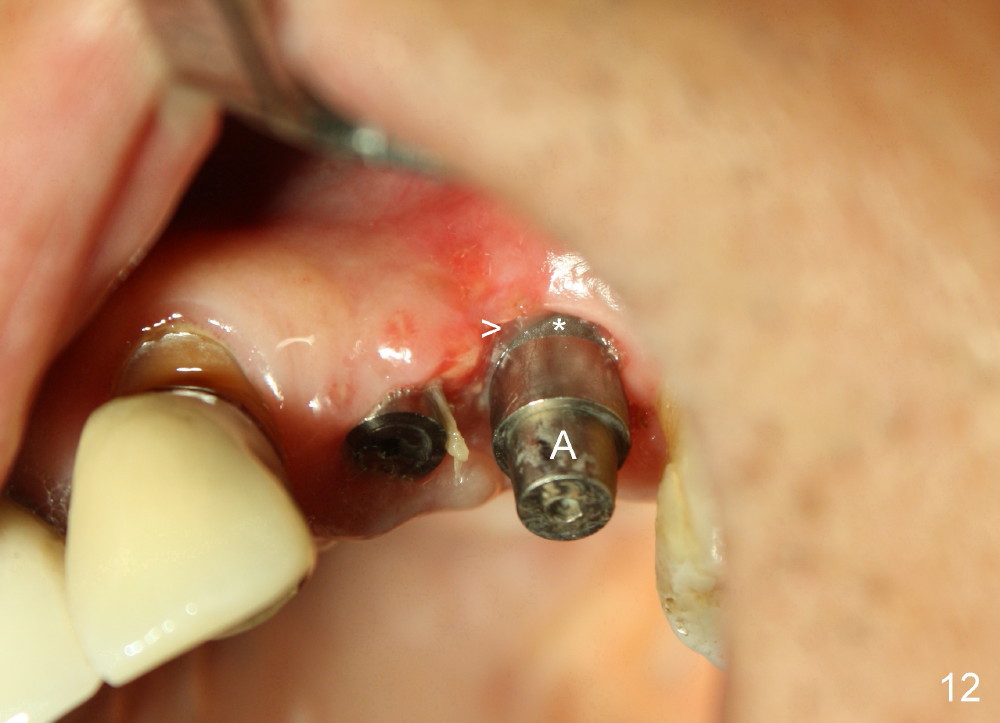

The perio dressing dislodges 18 days postop (Fig.12).  By that time, the extraction wound has healed.  The exposed rough surface of the implant (*) is most likely to be covered by fresh and healthy granulation tissue (>) underneath the gingiva.  Subsequently the abutment (A) is removed, since it has finished its temporary function.